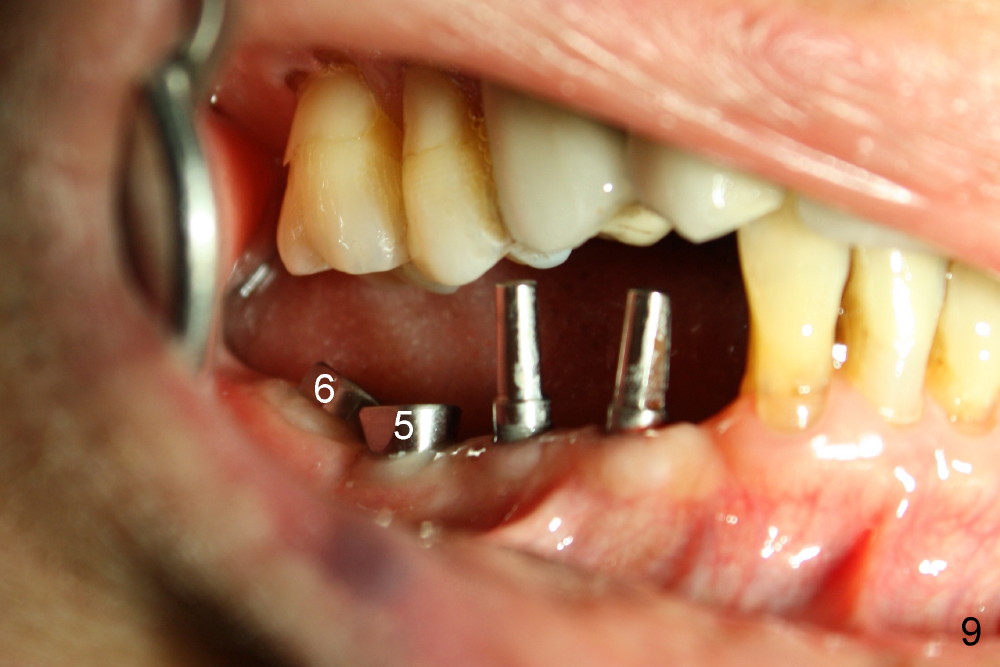

Four months after implantation, the gingiva around these four implants is healthy (Fig.8).  Healing cuffs are placed over the implants #5 and 6 (Fig.9).  The trajectory for the one piece implants is within normal limit relative to the opposing dentition (Fig.9,10).